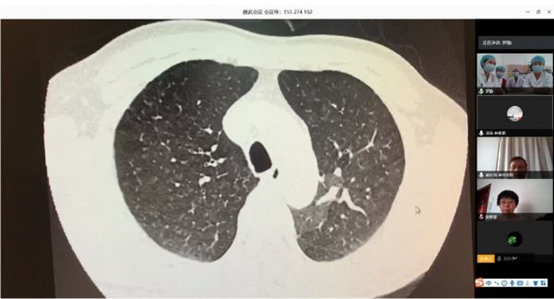

根據(jù)衛(wèi)健委新冠肺炎疫情防控工作總體部署以及醫(yī)院要求, 3月16日,北阜肺血管與血栓一病區(qū)和深阜肺血管病房已同步開始有序收治患者,開展包括右心導(dǎo)管、肺動脈造影及慢性血栓栓塞性肺動脈高壓患者的肺動脈球囊擴(kuò)張術(shù)等手術(shù)在內(nèi)的肺血管病所有診治。為減少新冠肺炎疫情傳播風(fēng)險,保證深圳肺動脈高壓患者得到最佳診療方案,北阜和深阜兩地肺血管病房充分利用“互聯(lián)網(wǎng)+醫(yī)療”的優(yōu)勢作用,開展遠(yuǎn)程線上查房,對每位患者資料進(jìn)行詳細(xì)分析,確定診治方案,使深圳的患者在疫情特殊時期可得到與平時同樣的醫(yī)療服務(wù)。